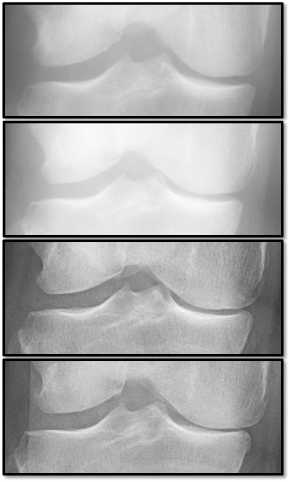

Refer to caption

(a)

(b)

(c)

(d)

Figure 5: Examples of attention maps for progression cases and the corresponding visualization of progression derived using follow-up images from MOST datasets. Here, subplots (a) and (c) show the attention maps derived using a GradCAM approach. Subplots (b) and (d) show the joint-space areas from all the follow-up images (baseline to 84 months). Here, the subplot (b) corresponds to the attention map a) and the subplot (d) corresponds to the attention map (c).